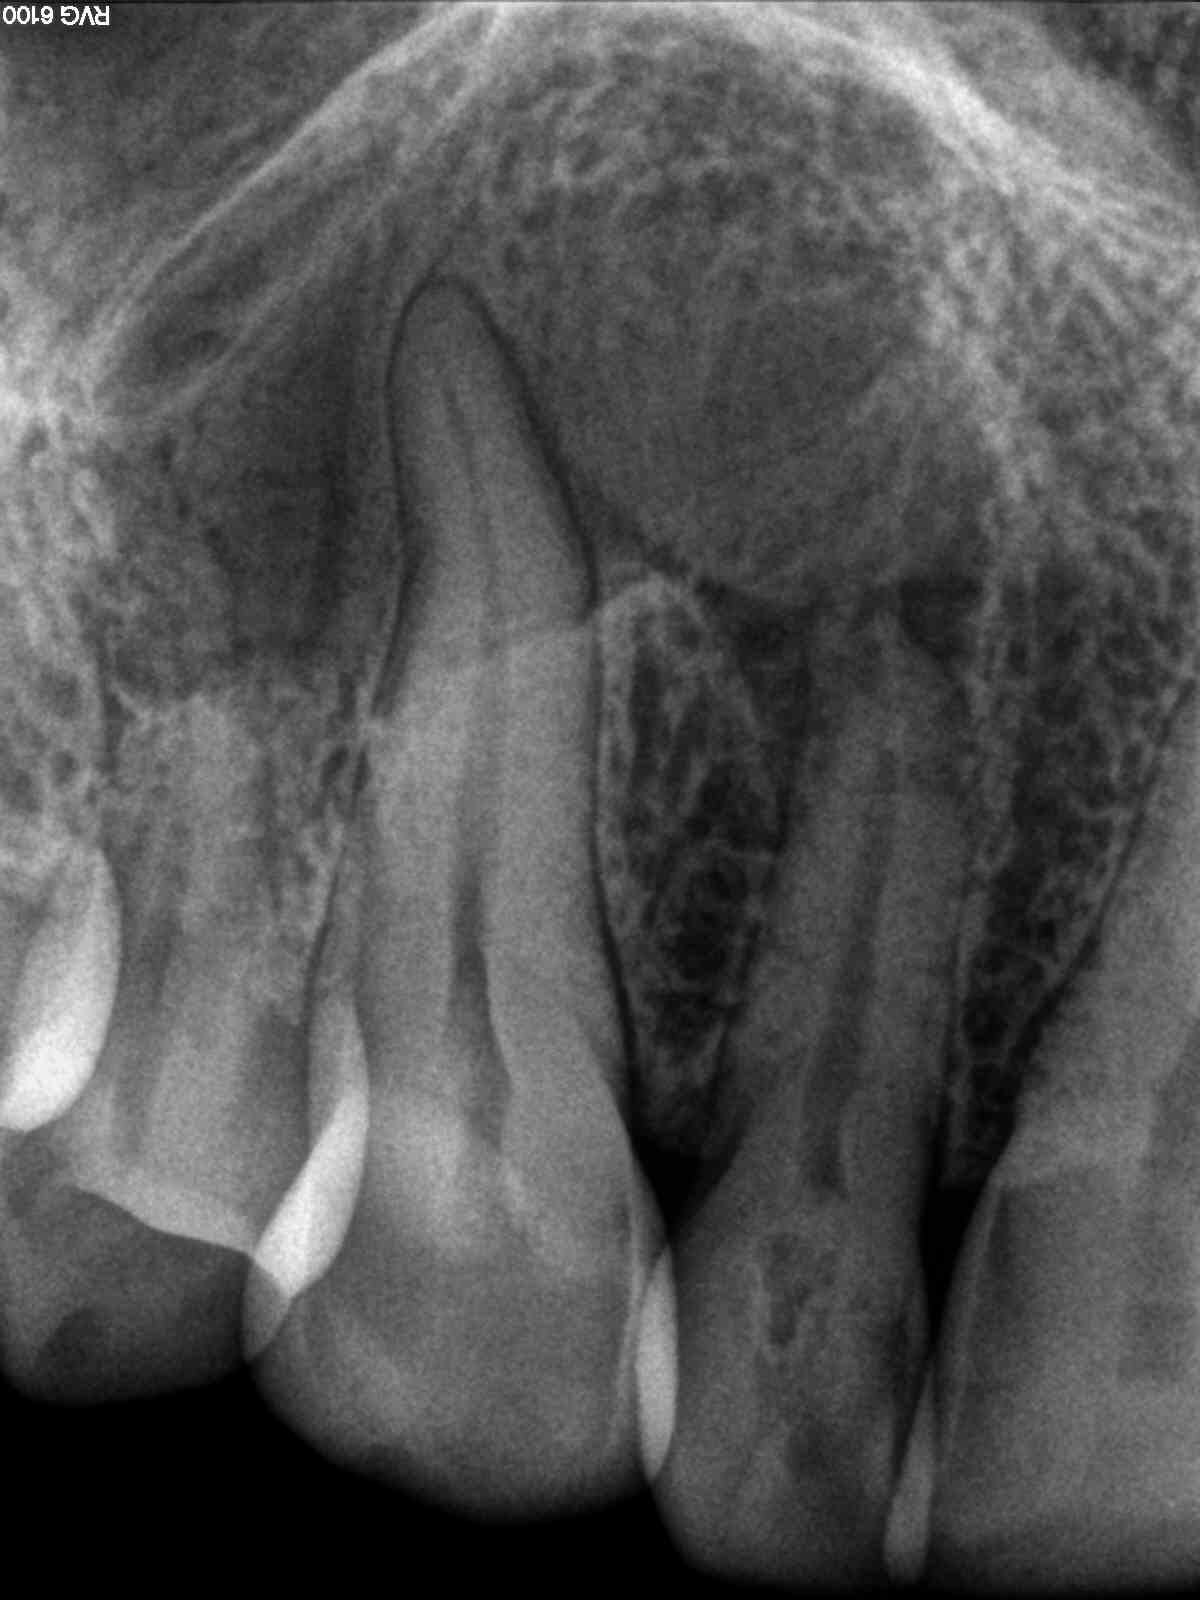

2D vs. 3D (XXXII)